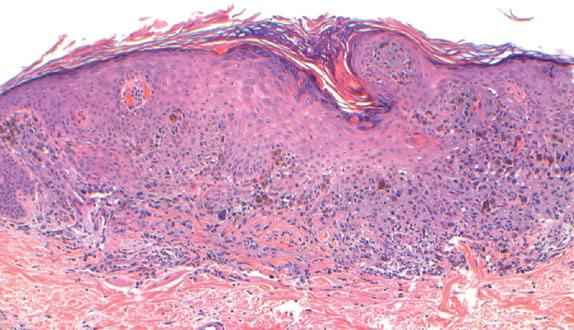

Histopathology. A characteristic histologic picture is seen in the epidermis and is referred to either as epidermolytic hyperkeratosis or as granular degeneration . It is present in bullous as well as in non bullous areas. There are variously sized clear spaces around the nuclei in the upper stratum spinosum and in the stratum granulosum. Peripheral to the clear spaces, the cells show indistinct boundaries formed by lightly staining material or by keratohyaline granules. A markedly thickened granular layer containing an increased number of irregularly shaped keratohyaline granules and compact hyperkeratosis is observed (14). When bullae form, they arise intraepidermally through separation of edematous cells from one another . The upper dermis shows a moderately severe, chronic inflammatory infiltrate. Mitotic figures are five times more numerous than in normal epidermis . Pathogenesis. Defects in keratin genes (KRT1 and KRT10) (16) are now known to be associated with this disorder. Mutations have been found in the carboxy terminal of the rod domain of keratin 1 and the aminoterminal of the rod domain of keratin 10 (17). The essential electron microscopic features are excessive production of tonofilaments and excessive and premature formation of keratohyaline granules; thus, at the periphery of the cells, numerous keratohyaline granules are embedded in thick shells of irregularly clumped tonofilaments (. The desmosomes appear normal, but the association of tonofilaments and desmosomes is disturbed, so many desmosomes are attached to only one keratinocyte instead of connecting two neighboring keratinocytes. Because of this disturbance in desmosomal attachment, blister formation takes place and real acantholysis occurs . Labeling with tritiated thymidine reveals greatly increased proliferative activity in the epidermis . It can be concluded that keratinization is both excessive and abnormal. Differential Diagnosis. Although the histologic picture of epidermolytic hyperkeratosis is diagnostic for the type of ichthyosis called epidermolytic hyperkeratosis, it is not specific for it. Hyperkeratosis is found also in several other seemingly unrelated conditions : epidermolytic keratosis palmaris et plantaris, solitary epidermolytic acanthoma, disseminated epidermolytic acanthoma, and linear epidermal nevus, usually of the systematized type. This latter entity was thought to be an entirely different condition than epidermolytic hyperkeratosis but with similar histologic findings. However, it is now known that epidermal nevi of the epidermolytic hyperkeratotic type are a mosaic genetic disorder of suprabasal keratin (l.e., point mutations of 10k alleles of epidermal cells in keratinocytes from lesional skin) that can be transmitted to offspring producing generalized epidermolytic hyperkeratosis . Epidermolytic hyperkeratosis can be an incidental finding in a variety of conditions